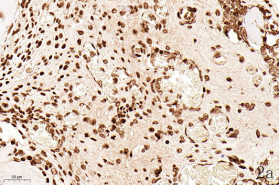

NDN(Necdin)属于黑色素瘤抗原(MAGE)家族,由60多个基因构成共享高度保守的MAGE同源结构域(MHD)[6,7]。最近几年的研究提出NDN是一种新的抑癌基因,其在卵巢癌[8]、乳腺癌[9]和黑色素瘤[10]等的组织和细胞系中低表达,过表达NDN可以抑制其生长,但NDN在骨肉瘤中的作用及机制尚不清楚。为探讨NDN在骨肉瘤中的作用及途径,我们收集了骨肉瘤患者的石蜡标本以及临床信息,对其进行了免疫组化检测及生存分析通过对骨组织和骨肉瘤HE染色发现,骨组织组,骨密质呈板层状,陷窝中可见骨细胞呈梭形排列( 图1 a 1b) ;骨肉瘤组,瘤细胞呈多角形,核大深染,核分裂多见,瘤细胞呈车辐状排列,瘤细胞间可见少量肿瘤性骨质形成(图1c1d)。同时通过免疫组化发现,NDN表达主要位于细胞的胞核中。NDN在骨肉瘤组织中的表达率为29.4%(15/51)(图1c1d),明显低于瘤旁骨组织阳性表达率80%(8/10)(图1a1b)。